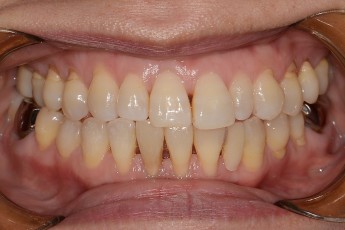

BEFORE & AFTER